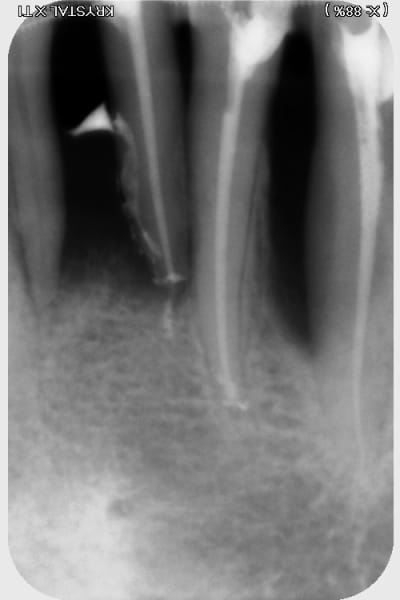

j'ai trouvé ça...rien de parfait malgré l'utilisation de broches manuelle, en alternance avec les rotatives sur certaines racine "légèrement coudées"....

pano et scan plus tard